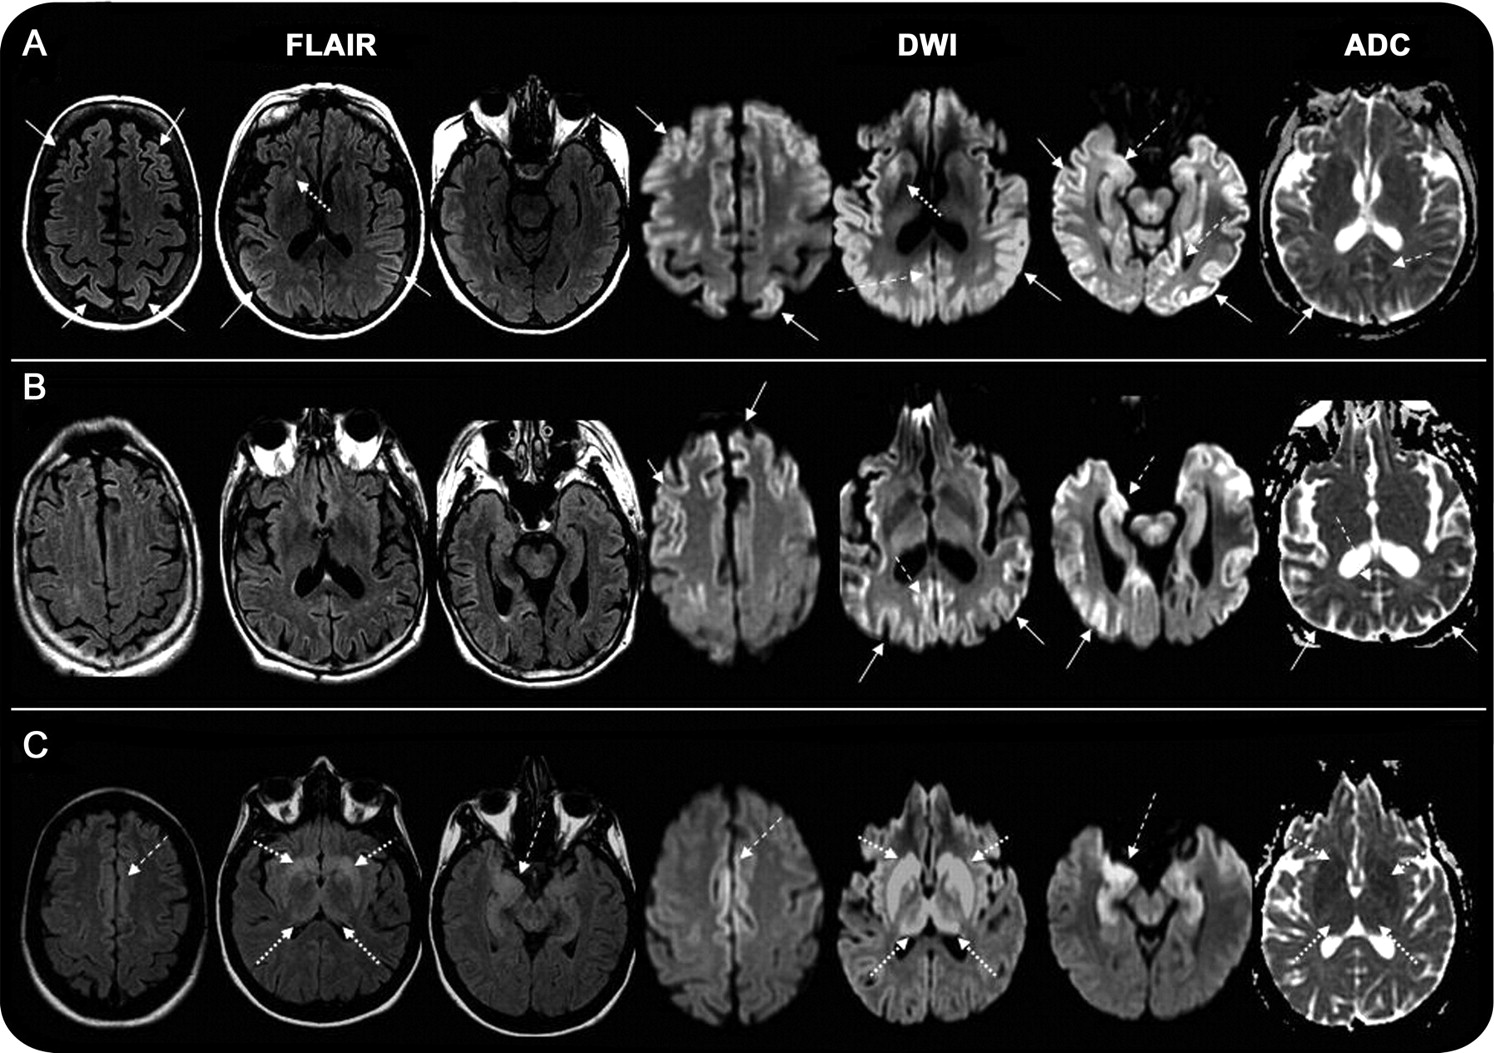

之间的区域的灰质参与不同sCJD和npRPD病人组(图1)。只有一个(见下文)患者sCJD在皮层灰质hyperintensities,边缘或皮质下区域或组合这些地区,但没有hyperintensity仅在边缘地区(表e - 3)。灰质异常sCJD总是比天赋更明显醉酒驾车,在某些情况下,指出只有在醉酒驾车。普通模式sCJD皮层,边缘,皮层下(54%)和皮层和边缘(27%)(图2、表e - 3)。没有明确的磁共振成像模式指出基于分子分类sCJD 129密码子多态性或朊病毒类型。13没有皮层参与sCJD病例的11%,包括VV2情况下,和单一MM2-thalamic案件没有显示灰质异常,与其他的研究一致。13,14

(一)皮层(实心箭头),边缘(虚线箭头),皮层下灰质(虚线箭头)。(B)皮层和边缘皮层。(C)边缘和皮层下。注意diffusion-weighted成像(驾车)显示了hyperintensities比相应的fluid-attenuated反转恢复序列(天赋),而醉酒驾车hyperintensities通常都有相应的表观扩散系数(ADC) hypointensity。模式被发现在54%的情况下,模式B在27%的情况下,和模式C在9%的情况下。注意,异常更容易出现在醉酒驾车,而不是天赋。ADC hypointensity,表明限制扩散,对应于大多数驾车hyperintensities。ADC异常是最容易识别的基底神经节。

只有9 29 npRPD患者(23%)有灰质hyperintensities异常;都是天赋上比醉酒驾车。都有边缘的参与。两个也有皮层下hyperintensities。7个孤立的边缘参与自身免疫诊断(图1和3)。确定皮层下醉酒驾车hyperintensities相关限制扩散或T2文风,读者调查了ADC地图在盲法评估。皮质下区域与醉酒驾车hyperintensity正常强度的ADC图npRPD患者(T2发光),但总是hypointense(限制扩散)在sCJD ADC图。

因为皮层hyperintensities被发现只有少数npRPD情况下,灰质参与详细解剖层次的百分比计算每个半球区域(31)只有在sCJD组。醉酒驾车,在较小程度上,天赋hyperintensities扣带,楔前叶,角,海马旁,优越和中间额叶脑回,尾状出现在sCJD 50%以上的情况下(图4)。不对称的参与被发现在大多数sCJD病例和尤为显著:在中央的皮层和扣带(图2)。半球也同样参与外侧额叶皮层下结构,但左半球是更频繁地参与顶叶、颞枕叶。有相对保守的中央前回,醉酒驾车hyperintensity仅3例(6%)。

在sCJD (fCJD),纹状体hyperintensity几乎总是显示一个渐进前后梯度下,主要涉及尾状(超过50%的病例)与后壳的相对节约(图2)。然而,后壳也很hyperintense在某些患者主要皮层下参与。ADC hypointensity是常见的pallidus皮层下sCJD为主的情况下,但伴随的醉酒驾车hyperintensity只在一个情况下(图2C)。